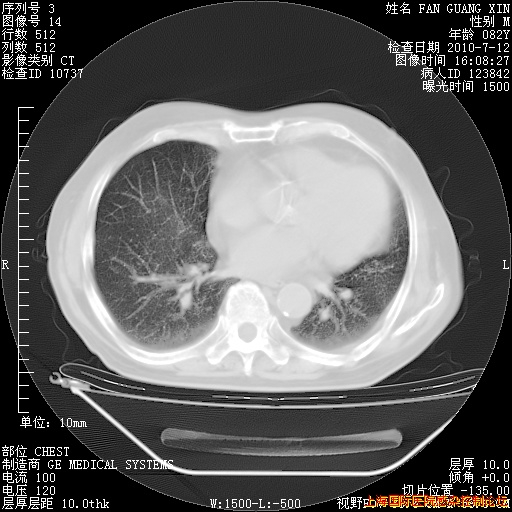

补发6月12日肺部CT肺窗

6月12日肺窗

整整相隔30天的肺部CT好像有所好转啊。甲强龙减量第3天,需要观察体温。